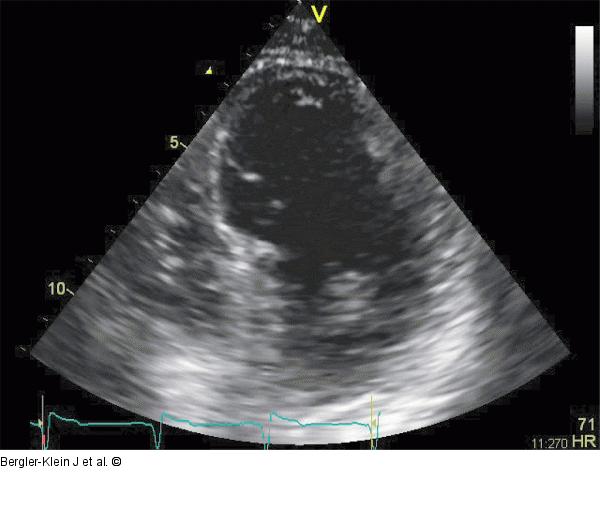

Abbildung 2: Akinesie - Apex Ausgedehnte Akinesie im Apex nach Vorderwandinfarkt mit verdünnter Myokardwand und Bildung eines Ventrikelthrombus. Apikaler Vierkammerblick. |

Ausgedehnte Akinesie im Apex nach Vorderwandinfarkt mit verdünnter Myokardwand und Bildung eines Ventrikelthrombus. Apikaler Vierkammerblick. |